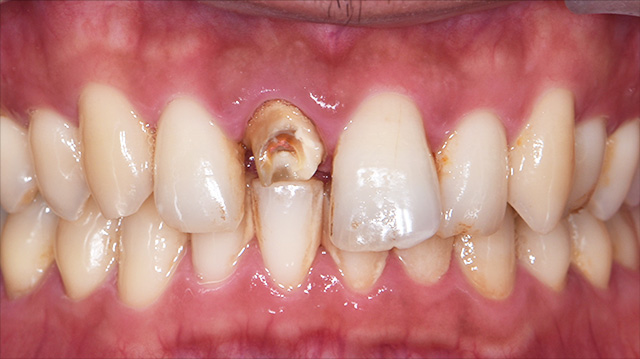

| 年代・性別 | 30代 男性 |

|---|---|

| 主訴 | 前歯の色が気になる |

| 治療期間 | 約1年 |

| 費用 |

仮歯 5,500円 × 2 ジルコニアクラウン 176,000円 × 3 インプラント 300,000円 インプラント仮歯 22,000円 サージカルガイド 70,000円 |

*キャンセルポリシーをご一読のうえご予約ください